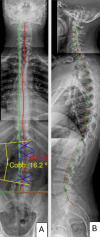

We present a case report of a patient suffering from chronic low back pain (CLBP) and chronic non-specific neck pain (CNSNP), both of which were caused and complicated by a physically demanding occupation, a history of mixed martial arts, and lumbar scoliosis. Improvements in patient-reported outcomes (PROs) and radiographic findings were observed following conservative spine rehabilitation. The patient, a 34-year-old male, had experienced chronic spine pain, particularly CLBP and CNSNP, for several years. He reported severe pain and increasing disability after a recent neck injury sustained while practicing jiu-jitsu. Radicular pain, along with numbness and tingling, was noted in the right upper extremity, extending to the first three digits, and there were also altered sensations and temperature changes in both feet. He described sharp, pinching mid-back pain and worsening disability due to the persistent pain, which led him to seek manual manipulative chiropractic spine therapy, though he reported little benefit from it. The patient had relied on over-the-counter pain medications for many years without achieving long-term pain and disability relief, and these medications were no longer used following treatment. Chiropractic BioPhysics® (CBP®) spinal structural rehabilitation protocols were used to improve coronal and sagittal balance, as well as paraspinal muscular strength, addressing posture, mobility, and related aspects. These protocols include postural exercises, postural Mirror Image® traction, and postural spinal manipulative therapy. All PROs improved, with a near resolution of all initial symptoms of chronic spine pain. Outcomes measured included disability indices and health-related quality of life (HRQoL) indicators. Radiographic parameter improvements were significant, demonstrating improved coronal and sagittal balance as a result of the treatment. Following 30 in-office treatments, administered three times per week for 10 weeks, initial outcomes were reassessed. The patient then received 13 in-office treatments periodically over one year, and all initial outcomes were repeated. The improvements remained stable over time. A 26-month follow-up found that the improvements were sustained over a very long period without additional treatment after the 13-month examination. Chronic spine pain, specifically CLBP and CNSNP, is a significant source of suffering and contributes substantially to the global burden of disease. Improvement in HRQoLs, PROs, and objective spine parameters are desirable clinical outcomes. Our case report documents objective improvement in lumbar scoliosis and spine pain, which is rare in conservative studies. This successful treatment of chronic pain with long-term follow-up contributes to the growing evidence supporting conservative, non-surgical treatments for CNSNP and CLBP. Successful management of chronic spine pain was observed in a patient undergoing CBP® treatment. The treatment was designed to address abnormal sagittal and coronal postural balance and radiographic abnormalities indicating spinal misalignment and reassess progress in PROs, as well as objective and subjective HRQoL measures, both following treatment and 13 months later. However, larger studies are needed to draw firm conclusions regarding the efficacy of this treatment for chronic pain.